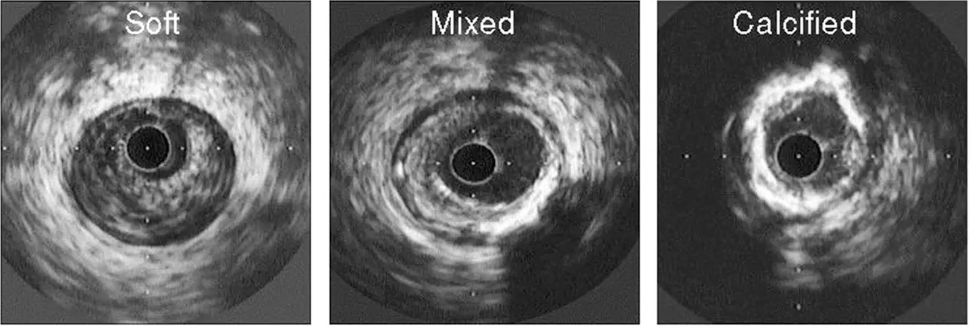

Types of plaque in OCT

Therapy for each plaque type in OCT

Lipid - Direct stenting Fibrotic - Compliant balloon Mild/moderate calcium - NC balloon Severe calcium - Atherectomy or shockwave